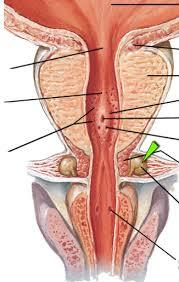

Bulbourethral gland (male)

Corpora cavernosa (pl.) Corpus Cavernosum (s.)

Corpus Spongiosum

Ejaculatory Duct

External urethral orifice (male)

Prostate gland

Prostatic/spongy urethra (males)

Seminal vesicle

Testis (s.) Testes (pl.)

Ureter

Urethra

Urinary Bladder (male)

Vas deferens (=ductus deferens)